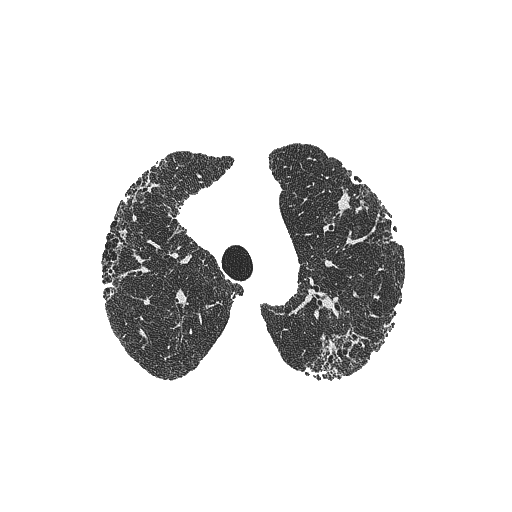

我在图像1上使用阈值掩码(图2)创建了以下图像(图3)。我试图使用opencv将图像3(肺)中央图像之外的所有像素转换为一种颜色(例如黑色)。基本上,这样我就只能在一个均匀的背景下(甚至是透明的)看到肺部的图像。我的问题是外部像素和图像3中肺内像素的相似性。这能用opencv吗?

cv2.imwrite('masked.png', masked_img)

cv2.imwrite('masked_transparent.png', masked_img_with_alpha)编辑:作为一个旁白,“透明度”基本上是一个掩码:值告诉你每个像素有多不透明。如果像素是0,它是完全透明的,如果它是255 (对于uint8),那么它是完全不透明的,如果它处于-中间,那么它是部分透明的。因此,最后使用的完全相同的掩码可以叠加到图像上,以创建第四个alpha通道(您可以使用cv2.merge或numpy进行堆栈),它将使掩码中的每0像素都完全透明;只需将图像保存为png以提高透明度。上面的代码创建了一个具有alpha透明度的图像,以及一个具有黑色背景的图像。

这里的背景看起来是白色的,因为它是透明的,但是如果您将图像保存到您的系统中,您将看到它实际上是透明的。FYI OpenCV实际上在imshow()期间忽略了alpha通道,所以您只会看到保存图像的透明度。